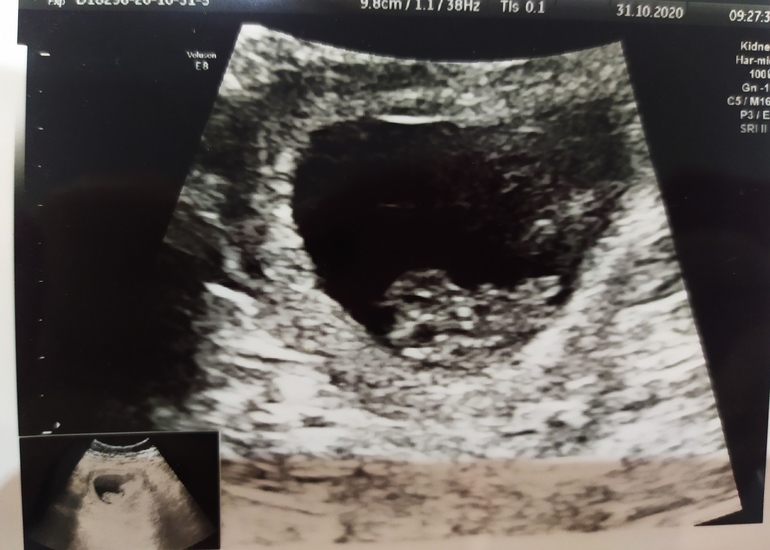

УЗИ 9 недель ❤

Сегодня была на УЗИ в 9 недель, до этого в 7, результаты есть в дневнике)) Пишу скорее на память и для девочек, кто любит сравнивать показатели))

СВД ПЯ 46 мм

КТР 22 мм

ЧСС 174 мм